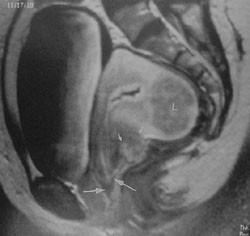

För säker diagnos är man fortfarande i hög grad beroende av laparoskopi. Den mest sensitiva, icke-invasiva avbildningstekniken är MR-teknik, som framför allt registrerar blodpigment. Metodens användbarhet begränsas dock av kostnadsskäl till de svårare fallen (fig 4).

För att öka möjligheten att upptäcka små lesioner bör man göra en tunnskiktsundersökning (ca 2 mm) av ett begränsat område med blockering av fettsignalerna. Detta önskemål måste specificeras på remissen. Lesionernas lokalisation och form har också betydelse: protruerande och cystiska förändringar syns bättre än platta härdar. Fibrosomvandlade härdar, som man t ex ofta har i sakro-uterinligamenten och kolon kan man oftast inte alls se (8). Inbuktningar i tarm- eller blåslumen kan ibland noteras. För cystdiagnostik används i första hand vaginalt ultraljud.